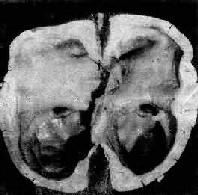

海马钩回疝

图16-7 海马钩回疝

左海马回内侧肿胀有深切迹(箭头),中脑右移变形,中脑右大脑脚受压,局部坏死出血(Kemohan切迹)